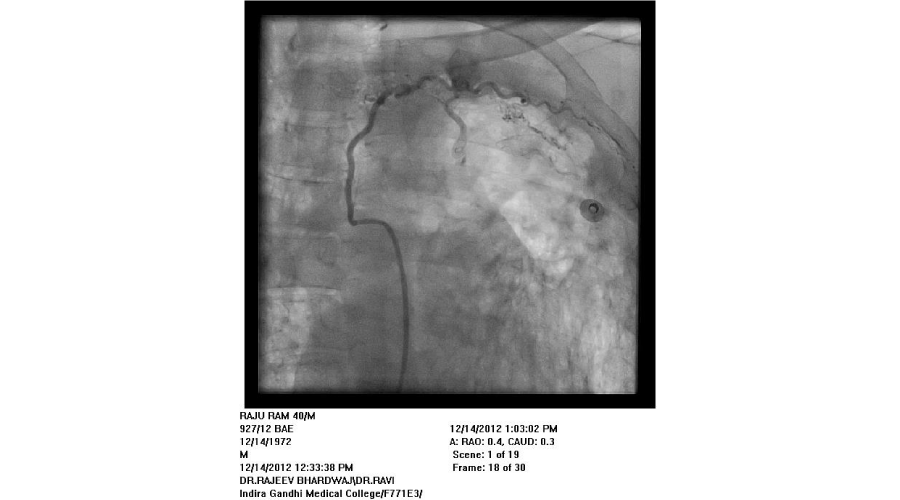

Patients admitted with moderate to severe hemoptysis in pulmonary medicine or general medicine department were the subjects of study. The patients were subjected to routine blood examination, X ray of chest, and CT scan of chest (Except in emergent situation). If required, bronchoscopy was done to localize the side of bleeding and for diagnostic purposes. Informed consent was taken from all patients. Commonest approach was from right femoral artery puncture. Seven French sheath was inserted in the femoral artery with the help of Seldienger technique. According to the protocol, bronchial arteries, intercostal arteries, subclavial arteries and its branches including the internal mammary arteries were selectively hooked with a catheter and contrast was injected into these arteries to see for the signs of bleeding. Initial attempt was made to see for bleeding source on the side suggested by X-ray or CT scan or bronchoscopy. Before the completion of procedure, vessels of other side were screened. If no bleeding vessel was found after screening on both sides, pulmonary arteriography was done with pig tail catheter to see for the source of bleeding from pulmonary artery. An artery was considered abnormal/ potential bleeder, if extravasation of contrast, aneurysm, increased caliber with tortuosity, vascular tufts, arterio-arterial or arterio-venous fistulas were seen. Once diseased artery was identified, it was selectively cannulated with a catheter. Most commonly used catheters were right Judikin, Cobra I, and Simmon I. The vessels were hooked deeply with the catheter, with the support of .018 inch guide wire. The vessel was then embolized with poly vinyl alcohol (PVA) particles mixed with contrast agent. The particles were injected till vessel was occluded or reflux of contrast was seen. If a vessel could not be hooked deeply, a micro-catheter was passed through the catheter and PVA particles were injected through micro-catheter. Size of particles used was 500-700 microns. If it was difficult to cannulate the branches of subclavian artery selectively, due to fibrosis, the artery was approached from radial artery puncture. Criteria used for successful embolization was that all diseased arteries were embolized. If spinal artery was seen on cannulation of a bronchial artery, the embolization was done distal to its origin to avoid inadvertent embolization of spinal artery.

We found that most of the cases required embolization of multiple vessels. In around half of the patients, both bronchial and systemic vessels required embolization. In around one fourth of patients, only bronchial and in another one fourth, only systemic vessels were the source of bleeding. In contrast to other studies, out of 192 vessels embolized, around 37% vessels were arising from subclavian arteries, (including 10% internal mammary arteries) and in 27% intercoastal arteries were the source of bleeding. Swansen et al., embolized the following arteries: right bronchial artery (34), left bronchial artery (11); combined right and left bronchial trunk (9); intercostal arteries (45); right internal mammary artery (8); left internal mammary artery (8); inferior phrenic artery (10); lateral thoracic arteries (3); thyrocervical trunk (2); and a left gastric artery (1) [11]. The complications of BAE in this study included subintimal dissection in two patients (4%), arterial perforation by a guide wire in one patient (2%), and reflux of embolic material into the aorta without adverse sequelae in one patient (2%). Pleuritic chest pain post procedure occurred in two patients (4%), shoulder pain post procedure in one patient (2%), and transient dysphagia in one patient (2%). One patient developed a groin hematoma at the puncture site.(Figures 1-5)